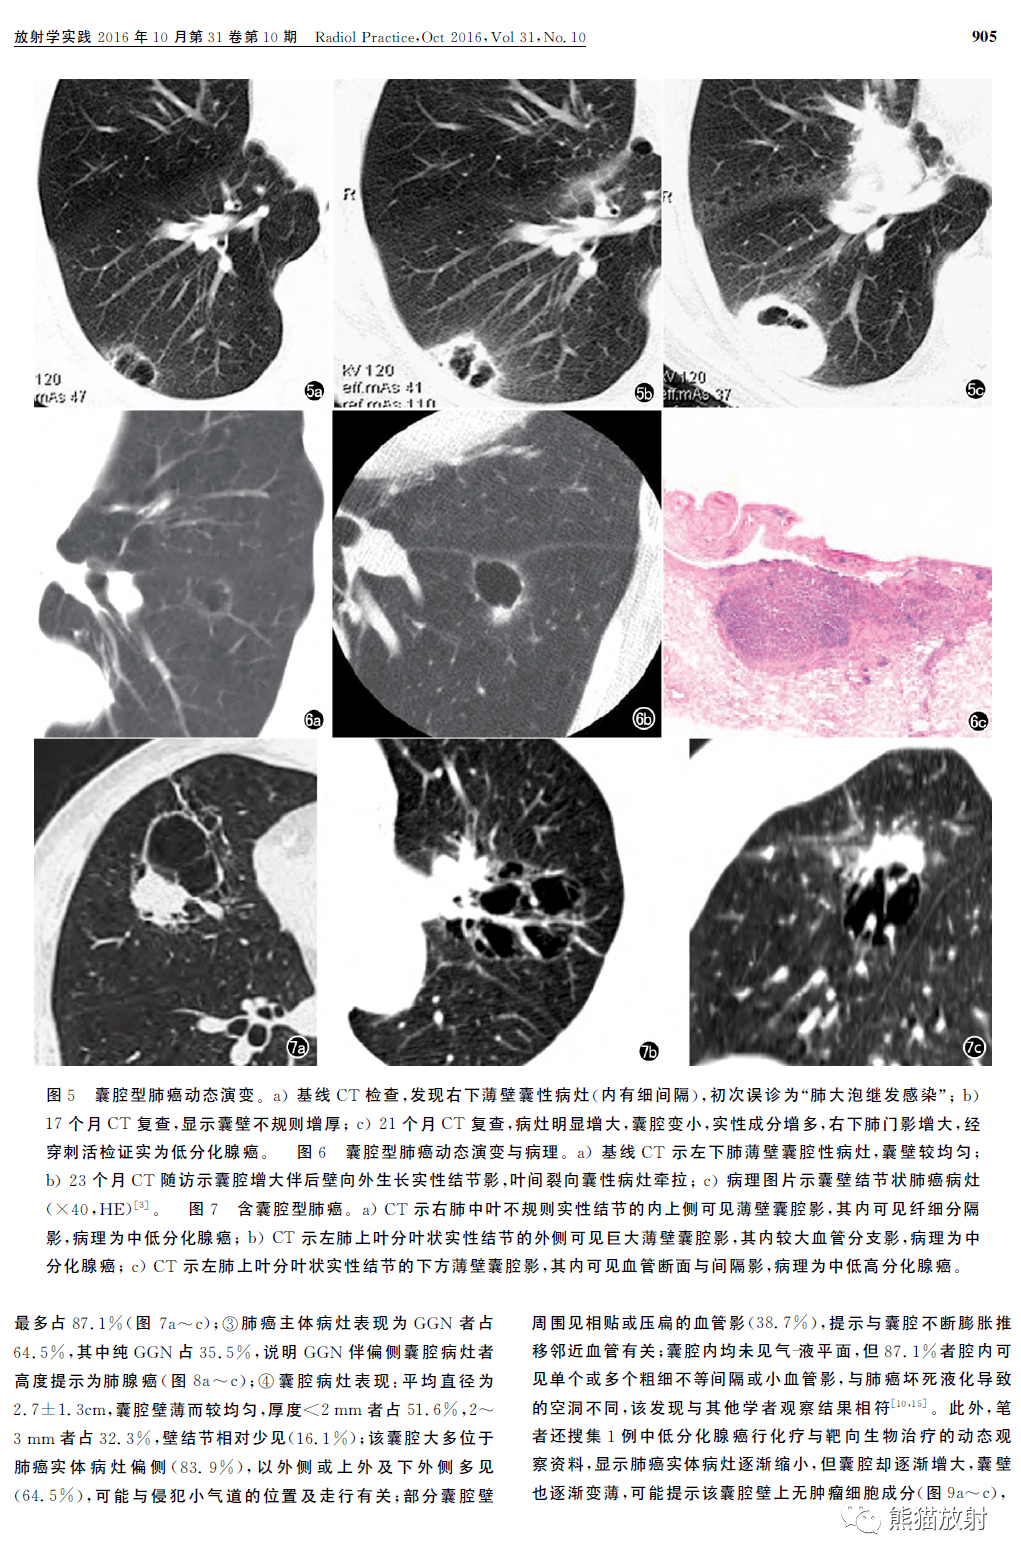

肺部囊腔类肺癌丨分型及其ct表现